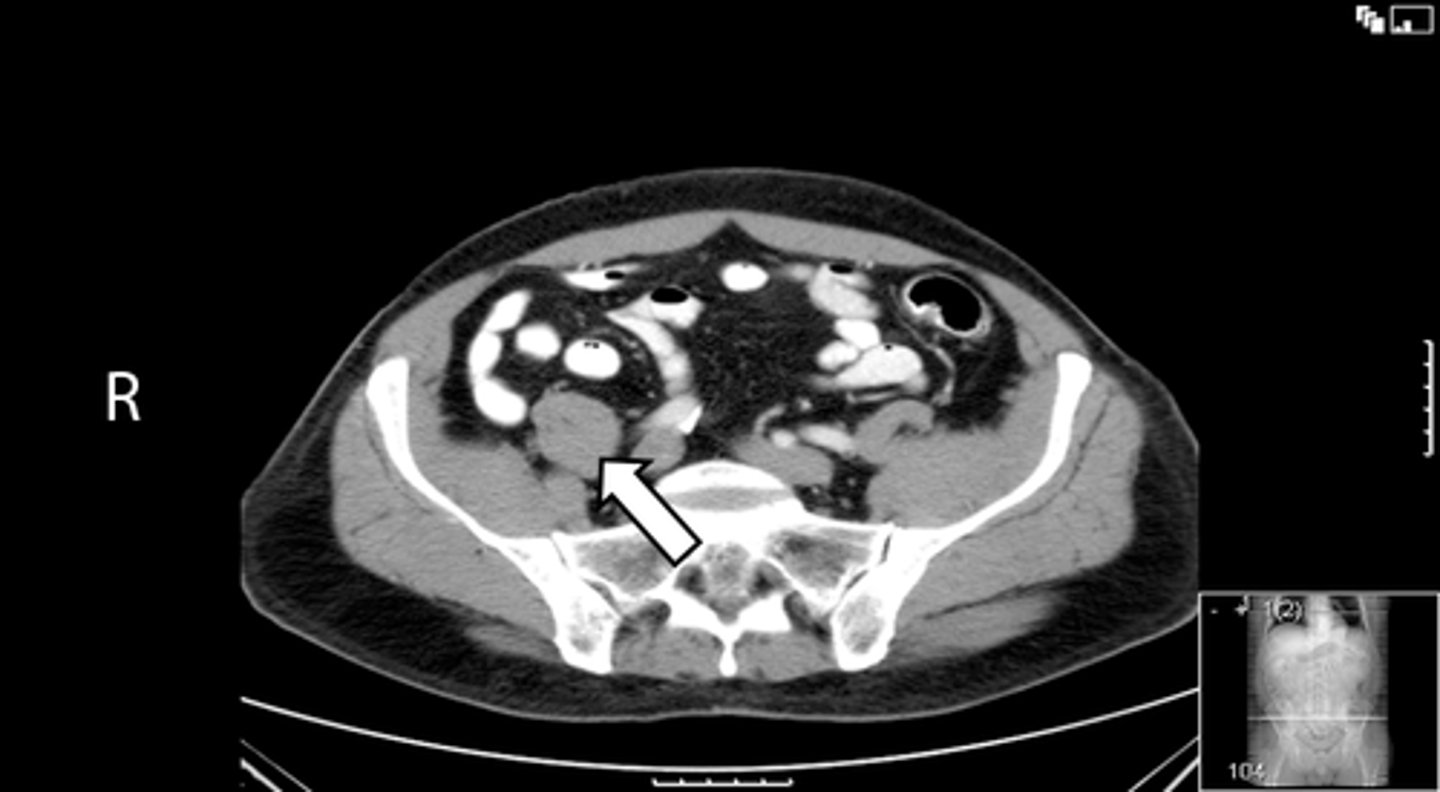

Axial bony pelvis CT

What is the image?

32

L ilium

What is indicated in the image?

<p>What is indicated in the image?</p>

33

New cards

L sacroiliac joint

34

R ilium

35

R sacroiliac joint

36

Sacrum